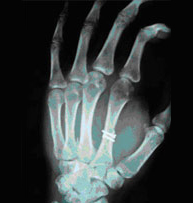

Las fracturas de los metacarpianos y las falanges suponen el 10% del total de todas las fracturas y más de la mitad se deben a traumatismos laborales. Es indiscutible la importancia que tiene una mano en nuestra vida diaria y ni que decir tiene que su recuperación exige de un conocimiento de la anatomía y biomecánica exquisita para poder diagnosticar y tratar adecuadamente sus lesiones. Son muy frecuentes las rigideces por tratamientos inmovilizadoresprolongados por lo que proponemos técnicas mínimamente invasivas que permitan una movilización precoz y unareincorporación a la actividad cotidiana lo antes posible.